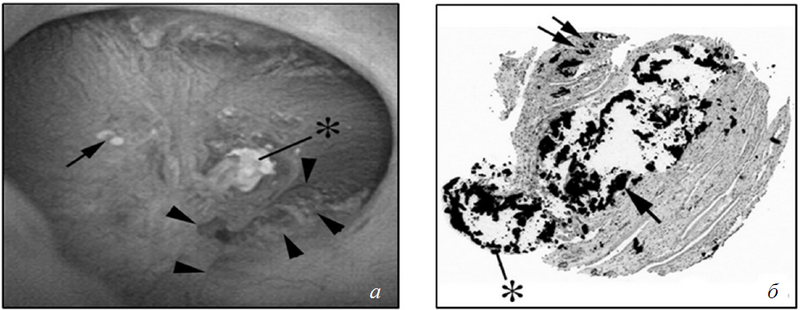

Это те самые «белые бляшки», которые можно увидеть во время эндоскопической операции. При этом подобные бляшки за счет особенности уротелия могут пролобировать в полостную систему почки и быть подвержены воздействию мочи (рис. 2). При этом речь идет об экспозиции мочой не кристаллов гидроксиапатита, но матрикса, в котором они находятся. Особенности обрастания камнем бляшки можно видеть, если получить мелкий камень с его тканевой основой (рис. 3) [12]. Зона нарастания камня на бляшке с самим камнем демонстрируют расхождение уротелия и отделение некоторых бляшек от ткани у основания камня. При визуализации бляшки методом трансмиссионной электронной микроскопии в нижнем правом углу заметны белые очажки гидроксиапатита внутри «бляшечного» матрикса. Сама бляшка окаймлена мантией из разрушенного матрикса и кристаллов гидроксиапатита.

Рис. 3. Ультраструктурные особенности мест прикрепления конкрементов в почках у пациентов с идиопатическими кальцийоксалатными конкрементами: а) эндоскопический вид конкремента размером 0,5 мм, прикрепленного к верхушке почечного сосочка на бляшке Рэндалла (стрелка); б) биоптат того же конкремента с подлежащими тканями; в) тот же комплекс ткань — конкремент после деминерализации. Обратите внимание, что конкремент отделен от подлежащей ткани (прямоугольник). Часть ткани все еще осталась в камне (звездочка), двойными стрелками обозначен клеточный детрит. Одной стрелкой указаны участки сохранившегося уротелия на почечных сосочках; г) бляшки Рэндалла (внизу справа), покрытые многослойными лентообразными структурами, состоящими из кристаллов и матрикса (вставка вверху справа). В очаге а определяются небольшие (звездочка) и крупные (стрелки) кристаллы, погруженные в мочу

Самый глубокий слой матрикса (вставка в верхнем правом углу) содержит протеины Тамма – Хорсфалла — свидетельство того, что матрикс бляшки изначально был покрыт органическим матриксом мочевого происхождения [12], так как интерстициальный матрикс в норме не имеет доступа к протеинам Тамма – Хорсфалла [17]. Как будто повторяя за частицами бляшек, кристаллы гидроксиапатита нуклеируют в чередующихся слоях матрикса — некоторые свободны от кристаллов, некоторые нет. На границе с мочой кристаллы смещаются в полость чашек и формируют основу-островок для будущего камня.